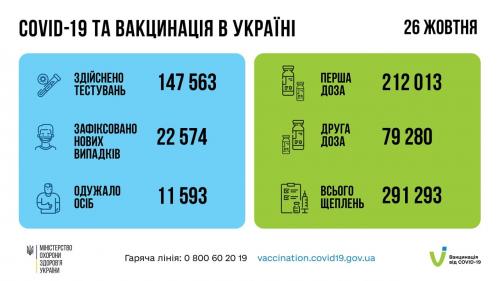

Пів тисячі - у важкому стані, 9 жителів Рівненщини померли за добу від коронавірусу